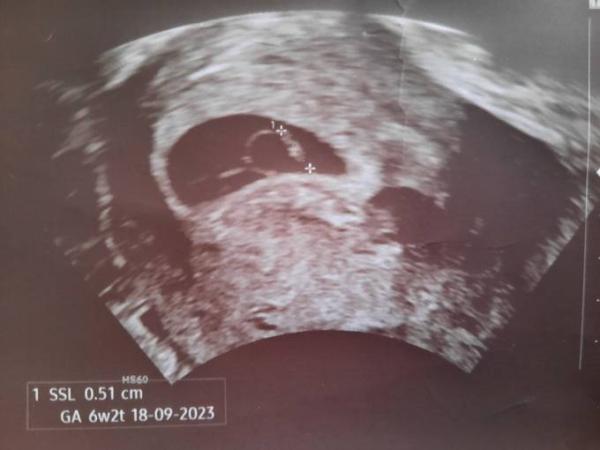

Hier mal mein Ultraschallbild. Weiss jemand ob die Distanz zwischen den cursor die richtige Distanz beträgt? Weil wenn man das hier nachmisst, wäre es größer...

Bild zu Embryo zu klein, eigentlich 7+4 - Schwanger - wer noch? Rund um die Schwangerschaft